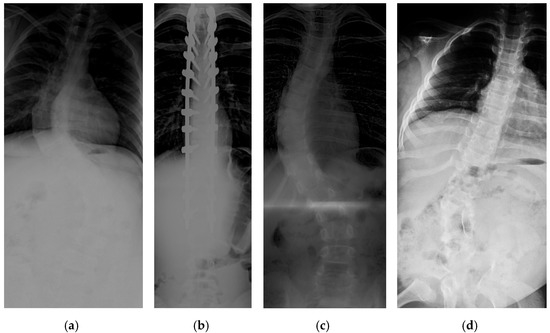

With the prevalence of degenerative diseases due to the increase in the aging population, we have encountered many spine-related disorders. Since the spine is a crucial part of the body, fast and accurate diagnosis is critically important. Generally, clinicians use X-ray images to diagnose the spine, but X-ray images are commonly occluded by the shadows of some bones, making it hard to identify the whole spine. Therefore, recently, various deep-learning-based spinal X-ray image analysis approaches have been proposed to help diagnose the spine. However, these approaches did not consider the characteristics of frequent occlusion in the X-ray image and the properties of the vertebra shape. Therefore, based on the X-ray image properties and vertebra shape, we present a novel landmark detection network specialized in lumbar X-ray images. The proposed network consists of two stages: The first step detects the centers of the lumbar vertebrae and the upper end plate of the first sacral vertebra (S1), and the second step detects the four corner points of each lumbar vertebra and two corner points of S1 from the image obtained in the first step. We used random spine cutout augmentation in the first step to robustify the network against the commonly obscured X-ray images. Furthermore, in the second step, we used CoordConv to make the network recognize the location distribution of landmarks and part affinity fields to understand the morphological features of the vertebrae, resulting in more accurate landmark detection. The proposed network was evaluated using 304 X-ray images, and it achieved 98.02% accuracy in center detection and 8.34% relative distance error in corner detection. This indicates that our network can detect spinal landmarks reliably enough to support radiologists in analyzing the lumbar X-ray images. Full article

Figure 1